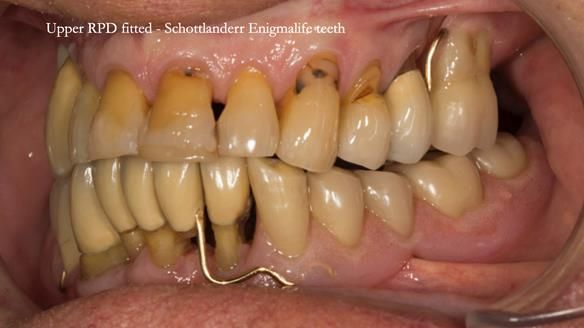

This case was always about function, not aesthetics.

Ken’s teeth were never going to look perfect.

There were stained composites, old restorations, and obvious wear.

That was accepted from the outset.

The way Rowan lengthened the teeth — particularly in the upper RPD — to match the existing gingival recession on the remaining teeth was superb. The dentures sit naturally within the context of the rest of the mouth.

Most importantly, Ken could eat comfortably, speak normally, and get on with his life without thinking about his teeth. There were no ongoing problems. No drama. No repeated interventions.